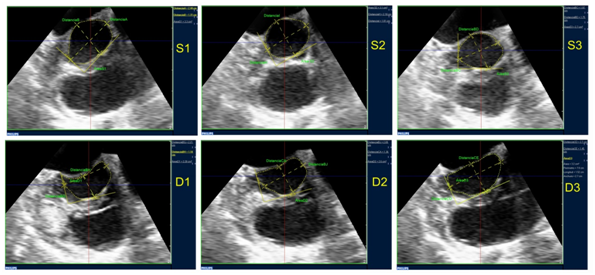

To assess the LVOT area, a QLAB 7.1 software (Philips Ultrasound) was used at a work station that was separated from the equipment. Upon exportation of the complete volume series to the work station, LVOT orthogonal cuts were performed, paying particular attention to achieving an angle of 90° with its long axis. Consequently, the references of the planes provided by QLAB (usually red and blue planes) were used, thus obtaining a short axis of LVOT in the third plane (green) (Figure 1).

LVOT short axis was captured at 2-4 mm below the annular plane. Three systolic and three diastolic phases were considered: protosystole (S1): beginning of the aortic valve opening; mesosystole (S2): maximun opening of the aortic valve; telesystole (S3): beginning of the aortic valve closure; protodiastole (D1): beginning of the mitral valve opening; mesodiastole (D2): partial closure of the anterior mitral valve during diastasis; telediastole (D3): partial opening of the anterior mitral valve via the auricular systole. Due to the movement of the cardiac cycle, an unbalanced in the cut plane was caused; it was adjusted to achieve a short axis orthogonal to the LVOT long axis in each one of the 6 phases. After the corresponding short axis was obtained for each phase, the LVOT area was measured by planimetry, assessed in cm². An average of the three acquired cycles for each phase was obtained. The shape of the LVOT short axis was assessed by visual estimation and by the larger/shorter diameter relation during the protosystolic and protodiastolic phases. Values were expressed in media ± DS, median and ranges.

Figure 1 Acquisition of LVOT orthogonal planes: LVOT long axis can be observed (red and blue planes) and its orthogonal view at the short axis (green plane). Measurement of the larger and shorter diameters and of LVOT area are obtained by planimetry of the short axis from the green plane.

Figure 2 LVOT planimetry obtained in the different phases of the cardiac cycle (S1: protosystole, S2: mesosystole, S3: telesystole, D1: protodiastole, D2: mesodiastole, D3: telediastole). In this case the modification in area and shape (partially elliptic during the systolic phases, semilunar during the diastolic) can be observed.